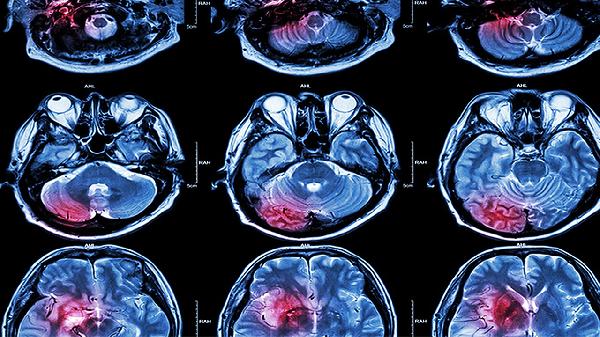

4、超声筛查:孕11-14周是筛查无脑儿的关键时期,通过超声检查可以观察胎儿头部发育情况。若发现异常,需进一步进行详细超声检查或胎儿核磁共振成像MRI以确诊。

5、羊水穿刺:对于高风险孕妇,医生可能建议进行羊水穿刺检查,分析羊水中的甲胎蛋白AFP和乙酰胆碱酯酶AChE水平,辅助诊断无脑儿。